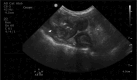

Background: Gastrointestinal eosinophilic sclerosing fibroplasia (GESF) in cats presents as mass(es) associated with the gastrointestinal tract, mesentery, and abdominal lymph nodes.

Results: The median age was 5.4 years (interquartile range [IQR], 3.3-8.9.); 30% were Domestic Shorthairs and 12% were Domestic Longhair cats, with the most prevalent pedigree breeds being Ragdolls (25%), Exotic Shorthair (10%) and Persian (8%) cats. The median duration of clinical signs was 90 days (IQR, 17.5-247.0); the most common clinical signs were weight loss (60%), hyporexia/anorexia (55%), chronic vomiting (37%), lethargy (35%) and chronic diarrhea (27%). Masses were located in the small intestine (32%), stomach (27%), ileocolic junction (15%), colon (10%), lymph node (8%) and mesentery (8%) and 15% of cats had >1 mass. Eosinophilia was present in 50% and hypoalbuminemia in 28% of cats. The mass was removed surgically in 37% of cases. Most cats (98%) were treated with corticosteroids. Survival was not statistically different between cats treated with surgical resection and cats treated with medical therapy alone, 88% of the cats were still alive at the time of writing.